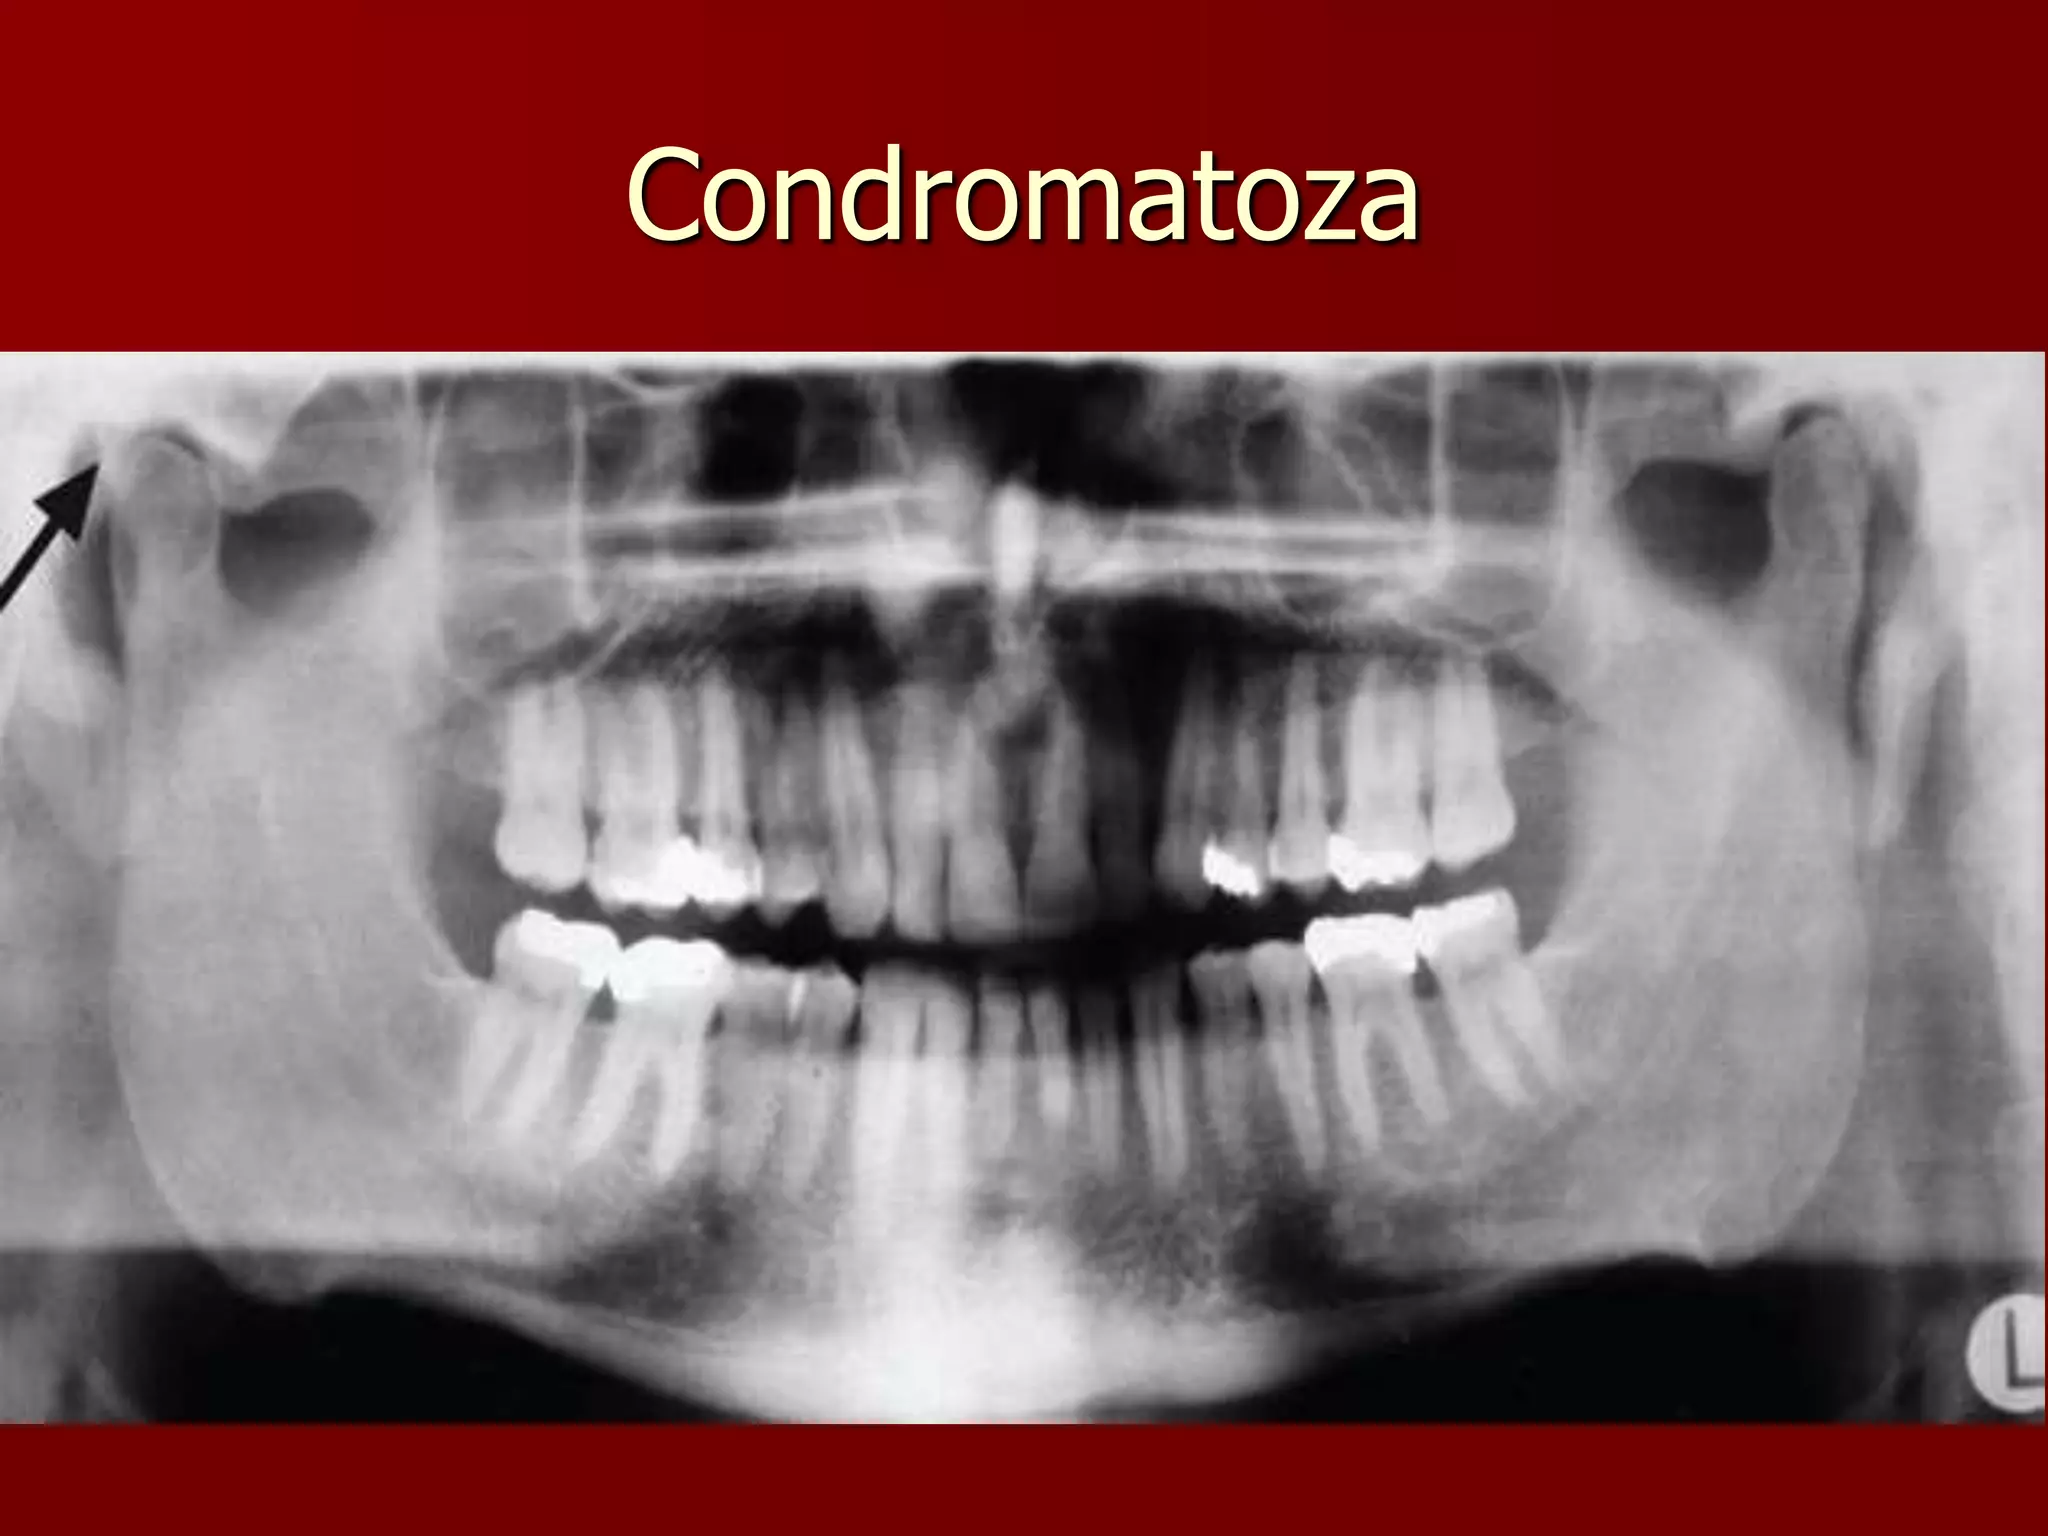

Osteocondrom

Condromatoza